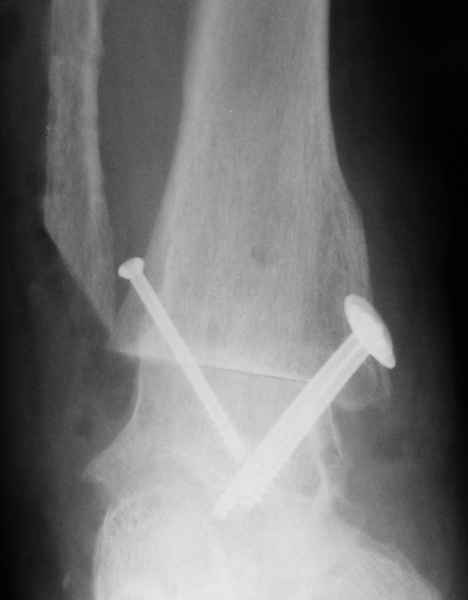

На фоне свищевой формы остеомиелита (скорее всего, речь идет об этом) о любой одноэтапной реконструктивной операции думать сложно. Если же все-таки решаться на одноэтапную операцию, то только убедившись, что гнойный процесс ограничивается внутренней лодыжкой. В этом случае возможен артродез с резекцией лодыжек (как на представленной рентгенограмме). Подобная операция позволяет относительно легко установить кости в оптимальное для артродеза положение, а также устранить гнойный очаг.

При поступлении произведено вправление вывиха, трансартикулярная фиксация голеностопного сустава спицами и ПХО раны.